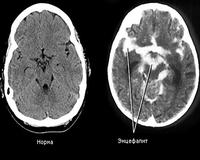

• МРТ головного мозга. Стандартная визуализация, использование контрастной МР-ангиографии и МР-венографии являются наиболее информативными методами диагностики, которые выявляют до 90% очаговых изменений в головном мозге при энцефалите. В качестве альтернативы можно сделать компьютерную томографию головного мозга.